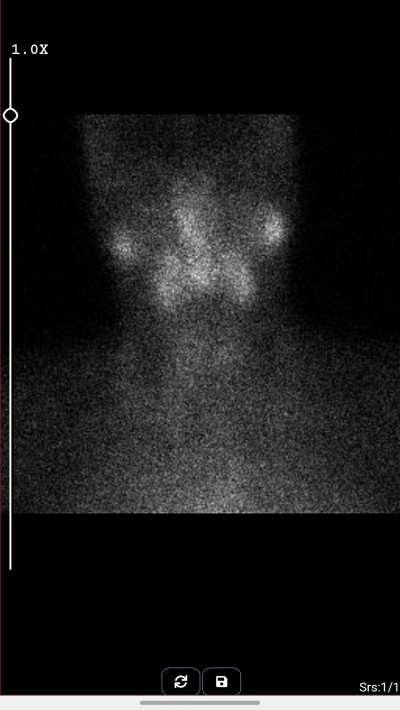

Ben bugün çektirdim anlayan var mı acaba

image